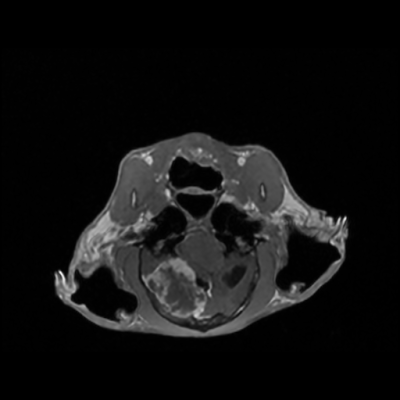

Meningioma

Mengiomas are typically benign and slow growing tumors arising from the meninges. They can occur anywhere along the CNS, but are most common around the brain. Meningiomas have a few key identifying characteristics:

- Vivid contrast enhancement

- 'Dural Tail' sign

- Compression or herniation of other brain structures

- Hyperostosis (bony overgrowth) of the cranium by the tumor